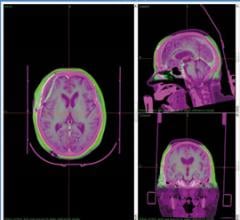

With the precision afforded by today’s radiation therapy delivery systems, treatment planning software that helps direct ...